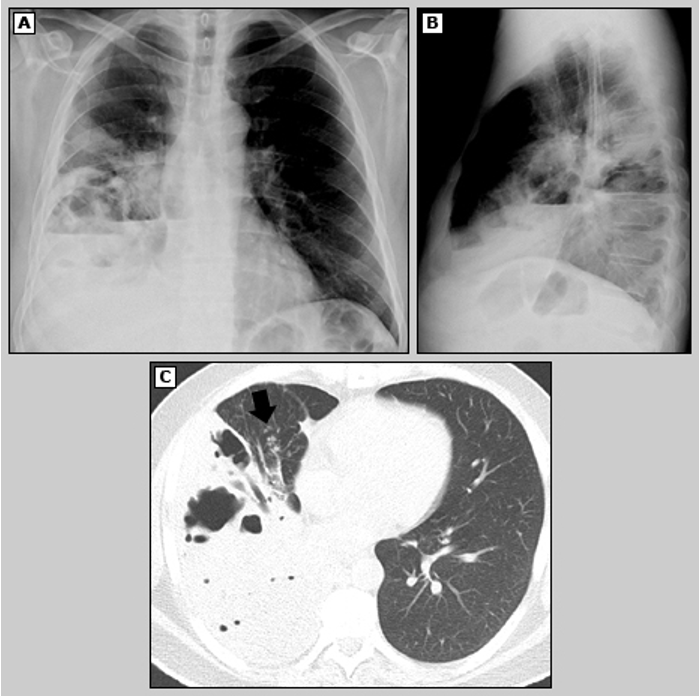

Rx tórax

A

Estudio inicial

Unilateral

Signo de la canasta

Segmento superior, lóbulo derecho

Hematógeno: disminución bilateral en lobulos inferiores

How well did you know this?

13

Q

TAC de tórax

Mejor definición de l a lesión

Distinguir en lesión parénquima y pleura